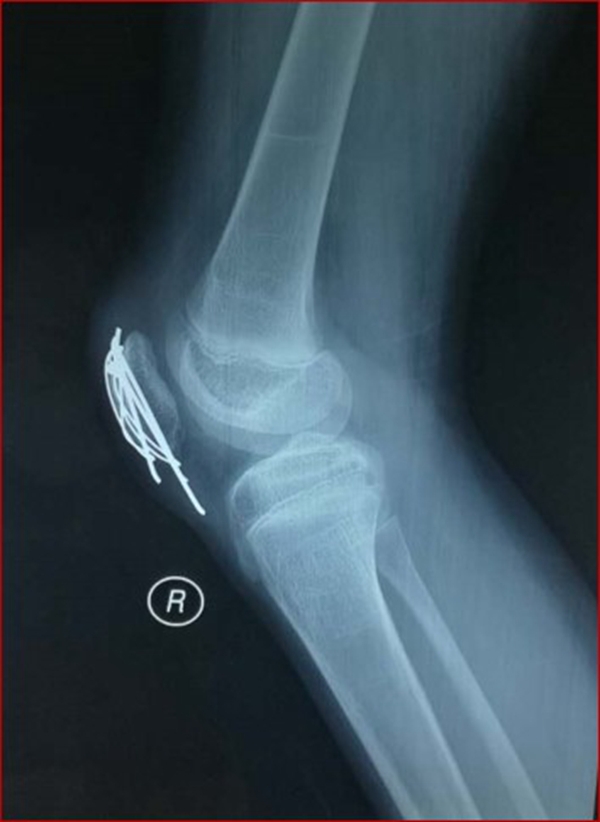

图1 受伤当时X线片

考虑此患儿伤后已3周,组织全科讨论,确定诊断为:髌骨上极陈旧性套状撕脱骨折。充分与家属沟通远期预后。